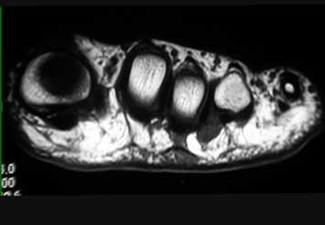

Resonancia magnética donde se evidencia el neuroma en el 3er. espacio intermetatarsiano.